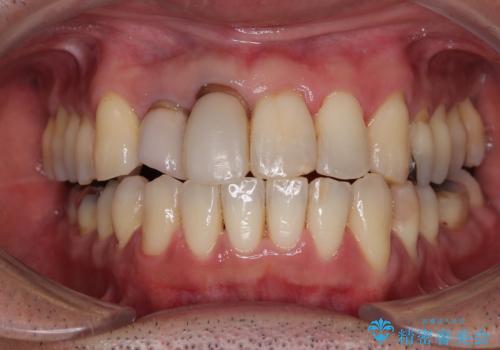

隠れている前歯 インビザライン矯正治療と前歯のセラミック治療

- 隠れるほどに内側に転位しいてる前歯を気にして来院された患者様です。

内側に転位していた前歯は、矯正治療では治しきることができませんでしたが、幸いにもオールセラミッククラウンに置き換える予定であったため、希望通りの仕上がりとなりました。